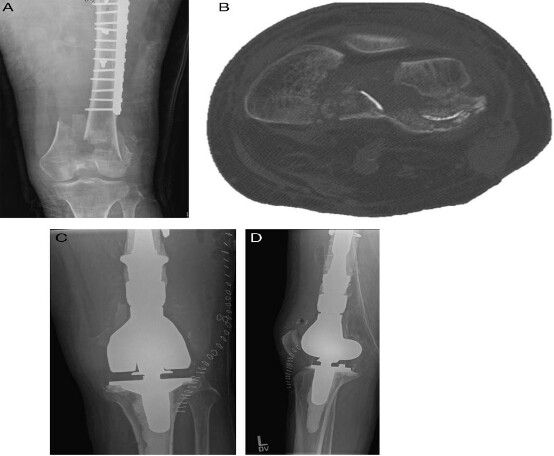

由于骨骼質(zhì)量較差、無(wú)法在鋼板和骨骼之間形成摩擦力,傳統(tǒng)的非鎖定鋼板很容易出現(xiàn)失敗。為了提高固定的穩(wěn)定性,鎖定鋼板技術(shù)被用于臨床,具有較高的潛力(圖 1)。和傳統(tǒng)的非鎖定鋼板相比,鎖定鋼板可以提供更好的穩(wěn)定性,具有更高的失敗載荷。但是,由于鎖定鋼板的遠(yuǎn)端更靠近關(guān)節(jié)面,遠(yuǎn)端螺釘容易對(duì)髂脛束造成刺激形成內(nèi)固定的并發(fā)癥。圖片1.jpg

圖 1 74 歲老年女性從幾個(gè)臺(tái)階上摔倒導(dǎo)致股骨遠(yuǎn)端開(kāi)放性骨折。A 為受傷的前后位 X 線;B 和 C 為術(shù)后 X 線:關(guān)節(jié)面完整性和股骨長(zhǎng)度、對(duì)線、旋轉(zhuǎn)得到恢復(fù)。由于存在大量的骨質(zhì)缺損,因此使用了抗生素骨水泥襯墊。D 為植骨加內(nèi)側(cè)鋼板加強(qiáng)固定術(shù)后 2 年的影像